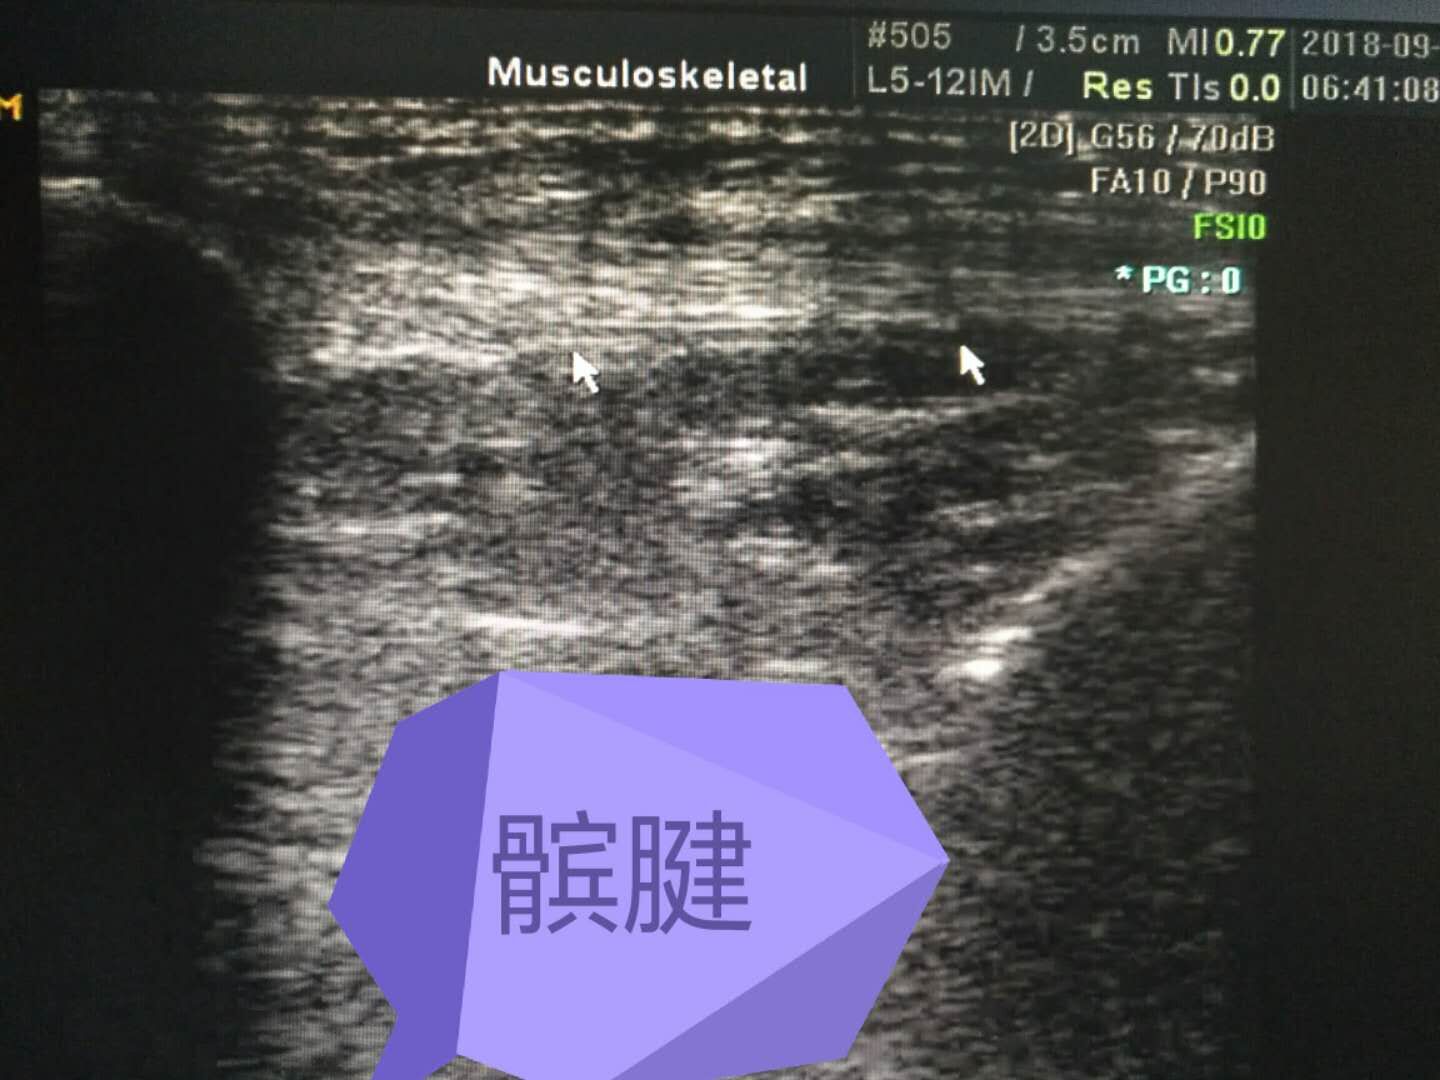

髕腱